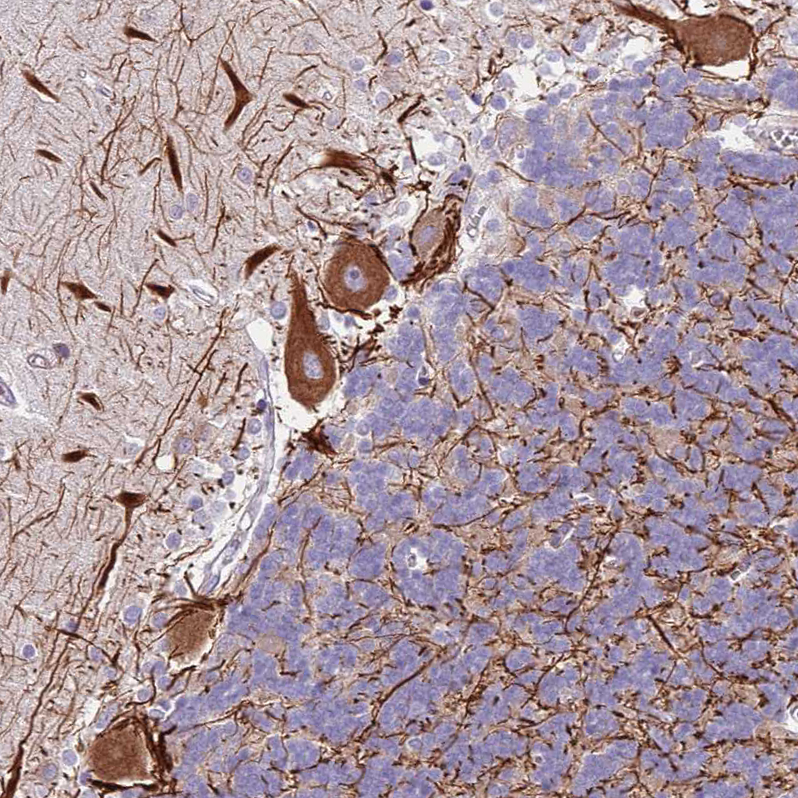

Immunohistochemical staining of human cerebellum shows strong cytoplasmic positivity in Purkinje cells.